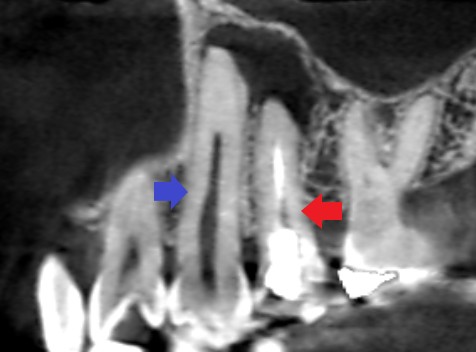

青い矢印の先が犬歯です。赤い矢印の先が、第一大臼歯です。犬歯には、膿の原因になりそうなむし歯や詰め物もされておらず、歯の神経に達するようなヒビもみられません。隣の第一大臼歯の膿が原因で犬歯の神経が壊死してしまったことが考えられました。